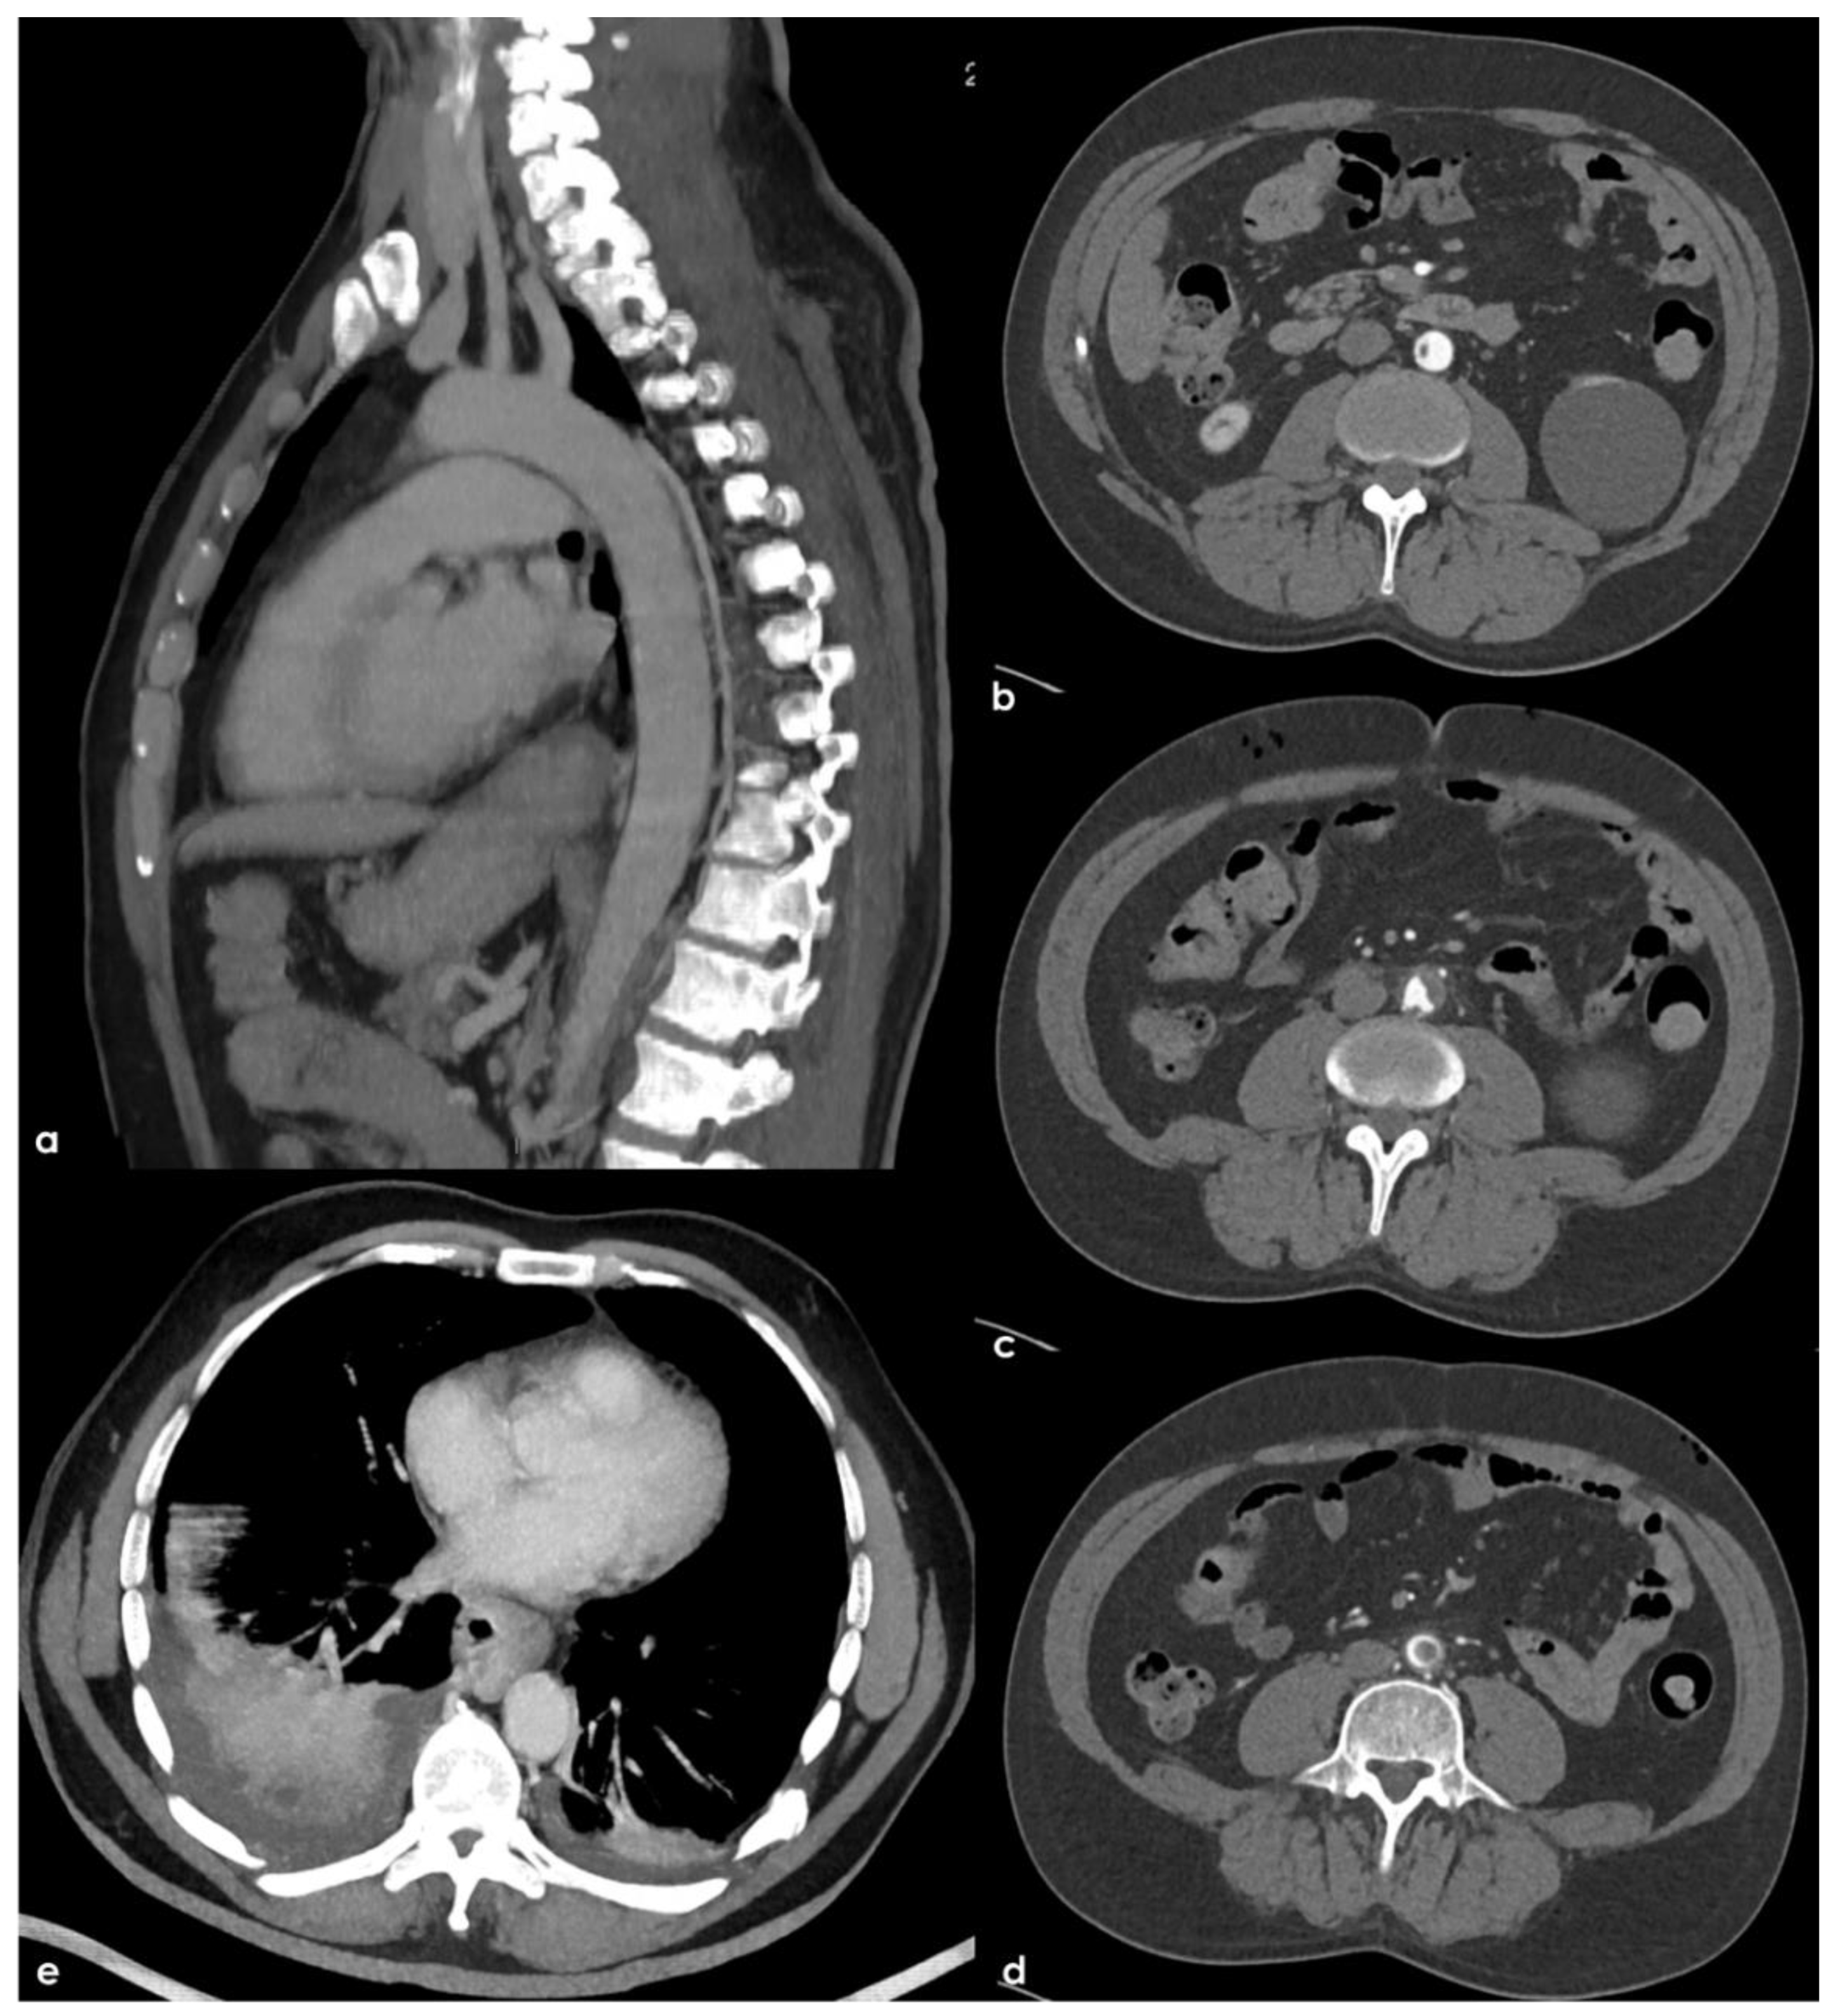

Further tests were carried out trying to identify other prothrombotic factors and to clarify the etiology of the clinical picture. The extended laboratory investigations included normal total (360.6) and unsaturated iron-binding capacity (283.6), transferrin saturation (21.3%), serum ferritin (39 ng/mL, normal range 22–275 ng/mL), serum iron (77 µg/dL, normal range 60–170 µg/dL) and transferrin (284 mg/dL). The fecal occult blood test was negative; nocturnal paroxysmal hemoglobinuria and hemolytic anemia were excluded, and the analysis of hemoglobin subgroups resulted within a normal profile. Antibodies anti-double stranded DNA, anti-mitochondrial (AMA), anti-smooth muscle (ASMA), anti-nuclear (ANA), anti-phospholipid, anti-deamidated gliadin peptide and anti-transglutaminase were within the normal range; the main onco-markers (AFP, CEA, CYFRA 21.1, NSE, PSA) did not express any significant pathological increase. Anti-thrombin levels were within the normal range, the search for a mutation of Factor V-R506Q was negative; a heterozygote genotype was identified for MTHFR-C677T, and an insignificant increase in homocysteine values was found. Transthoracic and transesophageal echocardiography as well as 24 h ECG monitoring were unremarkable. Conversely, a thoracic-abdominal CT scan highlighted thromboembolisms involving also the sub-segmental branches of both pulmonary inferior lobes and an 8 mm free thrombus adherent to a crescent-shaped atheroma of aorto-iliac junction and floating within the lumen (Figure 6).

Figure 6. Thorax and abdomen CTA with Maximum Intensity Projection (MIP) reconstructions. In (a), a sagittal plane view of the left half of the aortic arch and descending aorta demonstrated the disappearance of the thrombotic hypodensities previously seen (Figure 2). Consecutive axial slices of the pre-terminal segment of the abdominal aorta ((bd), rom cranial to caudal tip) showed a hypodense structure arising from a crescent-shaped structure in the aortic wall with atheromatous features and partially floating into the aortic lumen. The occlusion of sub-segmental branches of the pulmonary artery on both sides with a lung infarction on the right side is illustrated in (e).